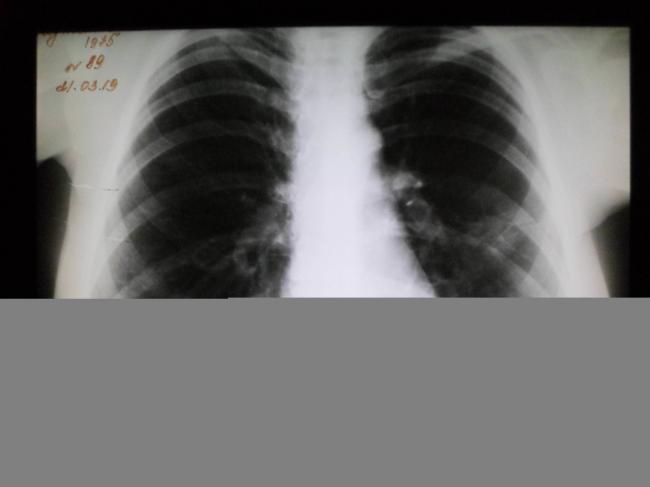

Помимо внешнего осмотра, сбора анамнеза, в том числе жалоб пациента, рентгенологического исследования легких, общего и клинического анализа крови, особое значение для подбора эффективной терапии имеют исследования, связанные с определением возбудителя болезни.

Почему после пневмонии держится температура 37°С? Обычно температура после прохождения полного курса лечения — это вполне нормально явление, если клинический анализ крови и показатели рентгена легких в норме.

Сначала врач ознакомится с жалобами больного, проведет осмотр пациента, оценит состояние его носоглотки. В обязательном порядке требуется проведение флюорографии. Пациенту необходимо сдать кровь и мочу на анализы. Кроме того, исследуется мокрота больного на микрофлору, что дает возможность определить ее характер. Ну и, конечно, следует проверить температурные показатели пациента. После того как будут получены результаты исследований, можно получить полную картину болезни и подобрать действенный способ лечения.

Важную роль при осмотре играет изучение носоглотки на предмет наличия гнойных воспалений. Также может потребоваться пройти флюрографию, чтобы изучить состояние легких после выздоровления еще раз.